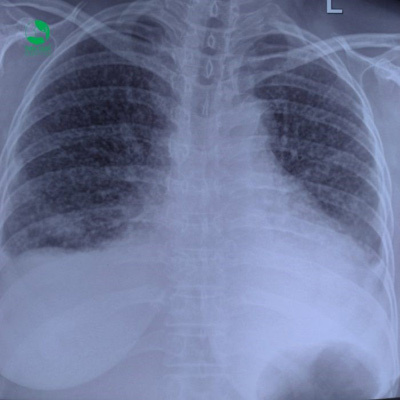

Kết quả kiểm tra tại Thu Cúc cho thấy các chỉ số ung thư trong máu cao vượt ngưỡng cho phép: CA 125: 214,4 IU/mL;CEA 30,03 ng/ML; CA 15-3: 50,1 IU/mL. Nguy hiểm hơn, phim chụp X-quang phổi của cô S. có đám mờ lan khắp 2 bên phổi “trắng như sao trên trời”. Sau khi sinh thiết, bác sĩ kết luận cô S. mắc ung thư phổi không tế bào nhỏ dạng biểu mô tuyến giai đoạn cuối. Để đưa ra phác đồ đặc hiệu, mẫu sinh thiết cũng được gửi sang Singapore làm xét nghiệm tìm đột biến gen và không thấy có đột biến.

| Đám mờ lan khắp 2 phổi của bệnh nhân S |